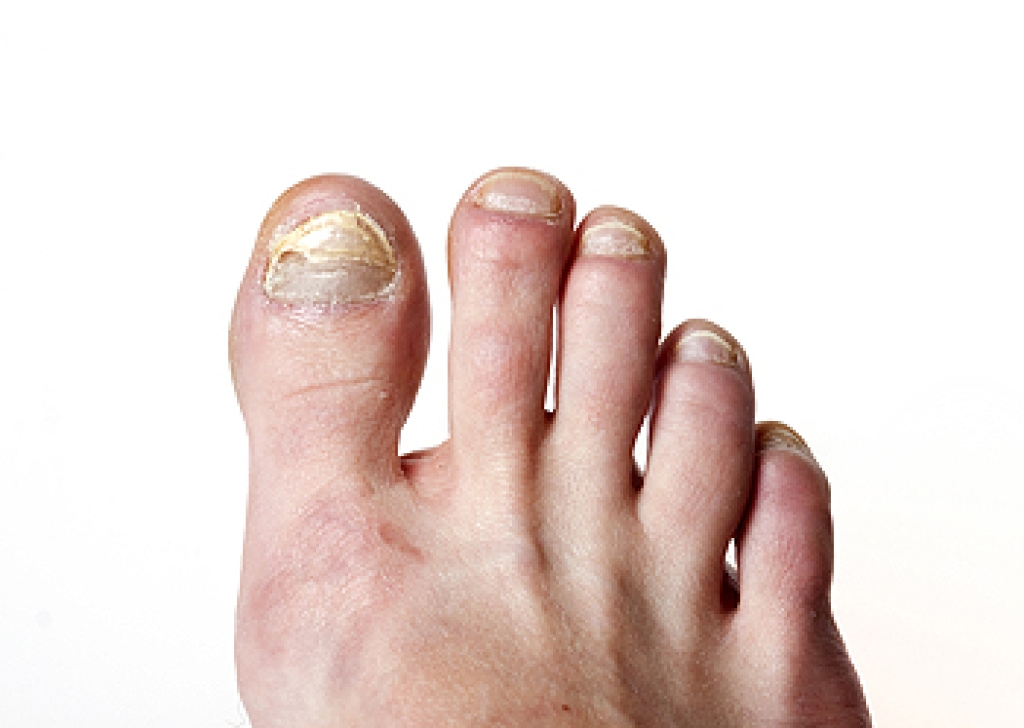

Limb salvage is the attempt of saving a limb, such as the foot from amputation. Podiatrists also try to make sure that there is enough function in the foot after the salvage that it is still usable. Diabetes is the number one cause of non-traumatic amputations in the United States. Those with diabetes experience poor blood circulation, which prevents proper healing of an ulcer. If the ulcer is left uncheck, it could become infected, which could result in the need for amputation.